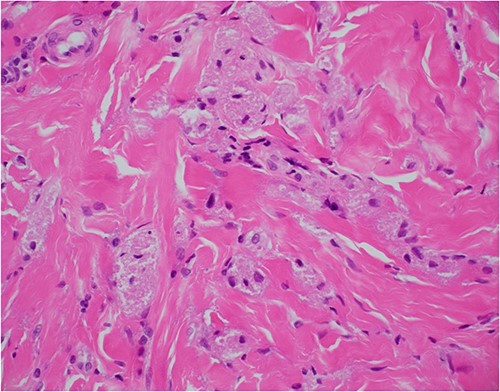

Haematoxylin and eosin stain, 400× magnification, showing tumour cell features of nests of epithelioid cells in the stroma with indistinct borders and granular pale eosinophilic cytoplasm.

Histologically, GCT typically contain polygonal cells that show numerous cytoplasmic granules [1, 2]. On immunohistochemistry, the cytoplasm stains positive for S100 protein [2]. Nuclear and cellular pleomorphism is absent, and mitotic activity is rarely observed [2]. The overlying epithelium of a GCT has on occasion been noted to possess pseudoepitheliomatous hyperplasia, which can sometimes be misinterpreted as squamous cell carcinoma if the biopsy size is too small, which can lead to misdiagnosis of a GCT [2].